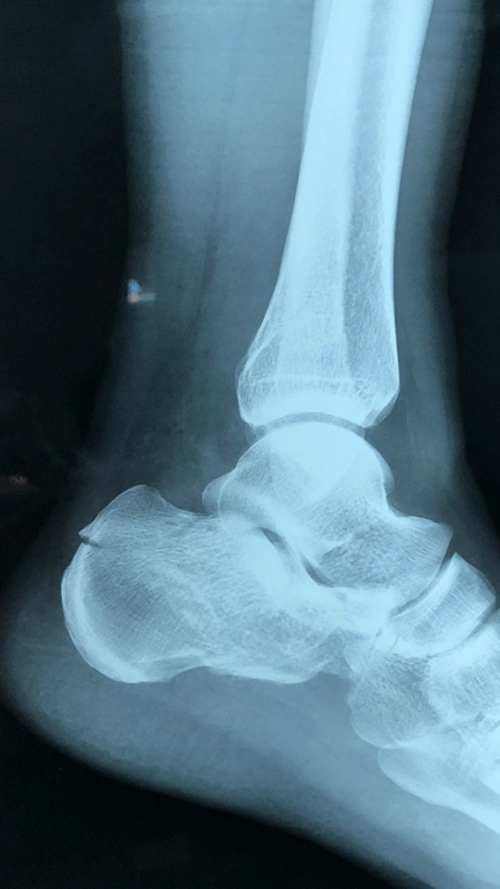

右跟骨骨折内固定术后

右跟骨骨折001a.jpg

一例跟骨骨折

请问右跟骨粉碎性骨折怎么治疗

跟骨骨折病例分享 - 好大夫在线

【原创】跟骨骨折一例报道